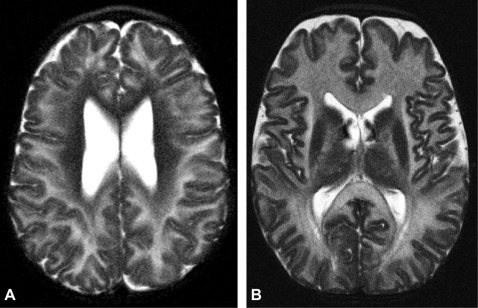

Through a combination of physical exam, brain imaging (MRI showing abnormal white matter), and a urine test showing high levels of N-acetylaspartic acid (NAA). Genetic testing confirms the diagnosis.